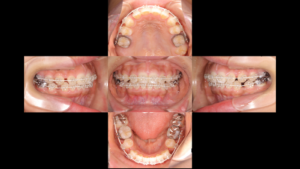

ここで状態の悪い歯を残したまま小臼歯だけを抜いて並べても、数年後にその奥歯がダメになってしまったら、また患者様は苦労することになります。そこで、リスクのある7番を抜き、一番奥に控えていた親知らず(8番)を矯正の力でスライドさせて持ってくるという計画を立てました。

僕としては、正直、親知らずをここまで動かすのは大変ですが、自分の歯で噛める喜びには代えられませんから、患者さんの喜ぶ姿と良い仕事をしたと思えるので頑張れます!

下にこれまでの経過を載せていきます。